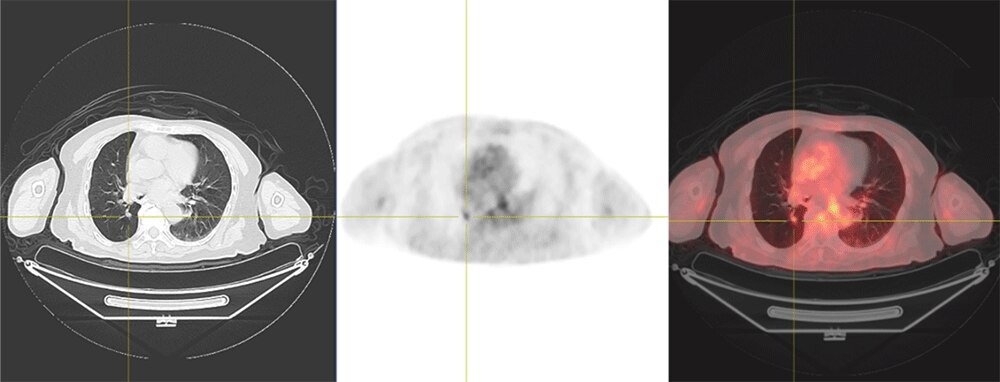

70代 男性 肺がん:術後脳転移に対する放射線治療後の全身検索目的でFDG-PET検査施行

約4mmの肺転移(SUVmax=0.84)

約9mmの肺転移(SUVmax=2.08)